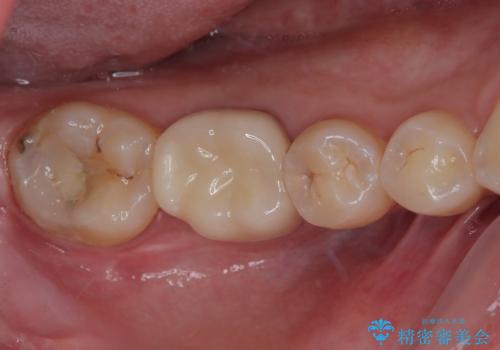

病変が消退しているかどうか、半年、1年とレントゲン写真で経過観察を行う必要があります。

海外に行かれていた都合で、術後2年での経過観察となりましたが、無事に病変の消失が認められました。